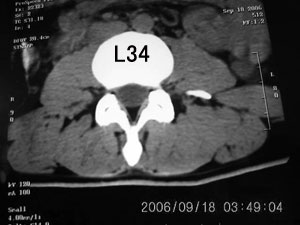

以下是引用守望可可西里在2006-9-18 21:29:00的发言:[br][br] 马尾肿瘤,密度较低,大部分似乎呈囊性变(看着很费眼),考虑室管膜瘤,建议mri。

以下是引用dyg在2006-9-18 22:27:00的发言:[br]正常脊髓.[br]分析:人的脊髓从枕大孔开始至腰1.2椎体为止,有2个生理膨大,分为颈膨大和腰膨大;该病人脊髓须然从腰段开始直至马尾似乎膨大,胆是与上段脊髓密度没有多大变化,所以我认为是正常膨大之延续;当然最好做ct增强或mri检查,排除肿瘤.

以下是引用飞虎在2006-9-18 20:18:00的发言:[br]部分椎管内密度不均且无ct值 故mri检查